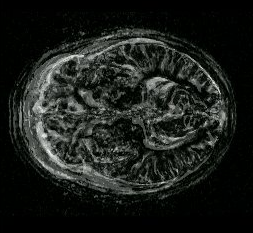

Figure: The image from Figure [*] rerendered for proper viewing

Image slice_recovered

The image of interest is one which shows the average over all shuffle difference images (volumes in this case). It can be seen in Figure [*], which represents the average of 8 shuffle difference images and is derived from images like the one in Figure [*]. In this case, it directly corresponds to it.